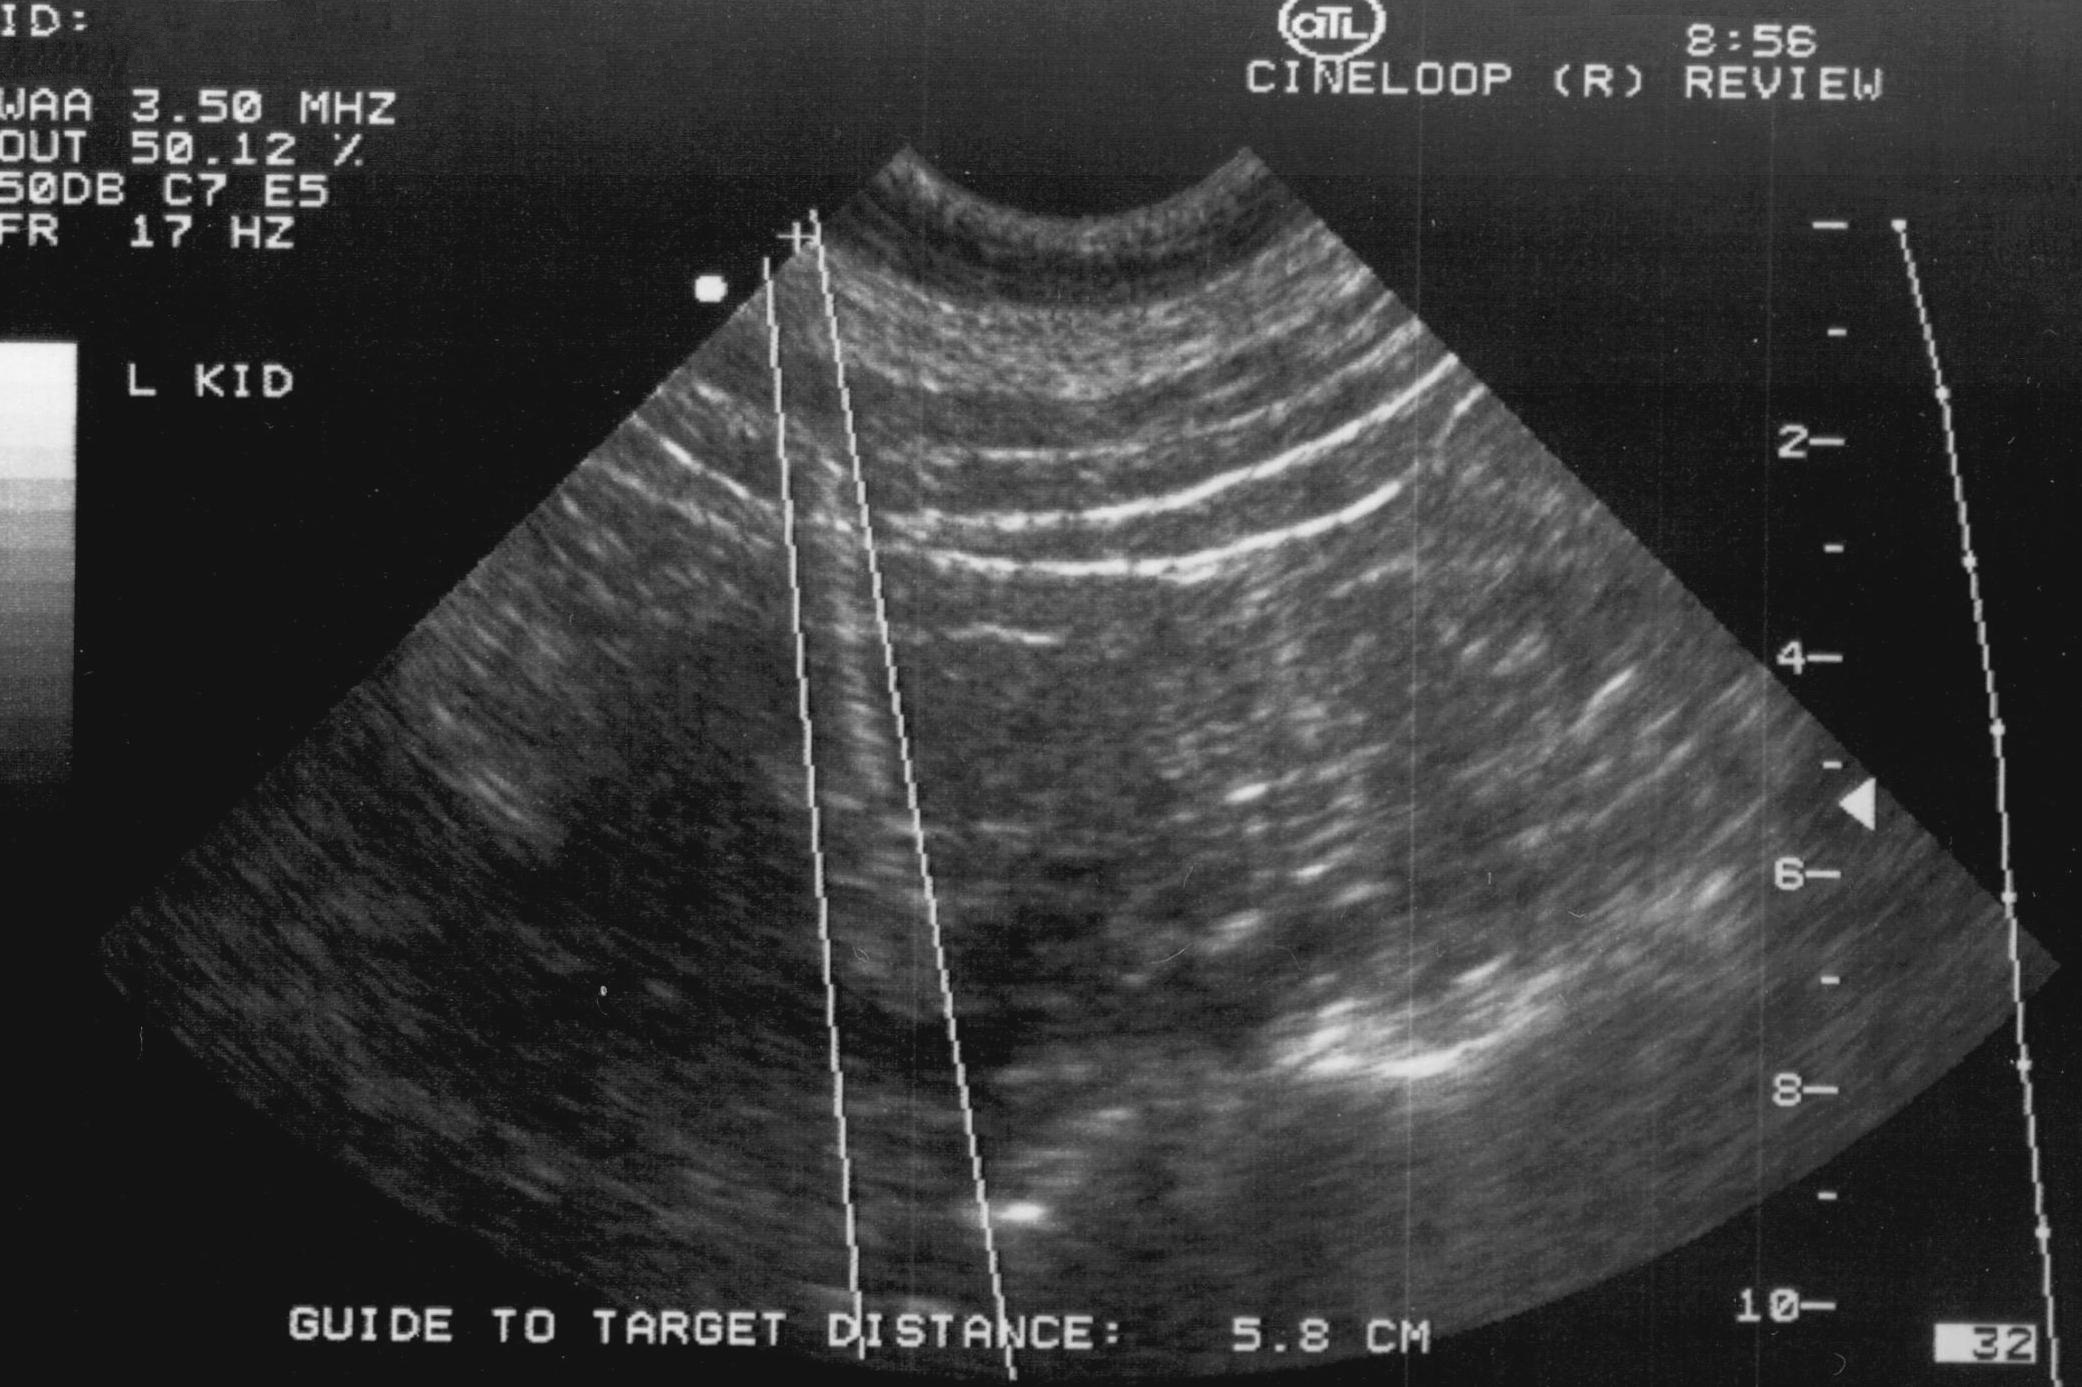

Nowadays it is the most commonly used method. Both superficial (figure 3.) and deep (figure 4.) lesions can be biopsied.

Figure 4. – US guided core biopsy (kidney)

The free hand method requires more experience from the operator. The needle should not move out of the transducer’s field of view, not to lose sight of its tip. Lesions lying 10-12cm deep in the body, with a diameter equal to or less than 10mm should all be approached with needle guiders for biopsy.